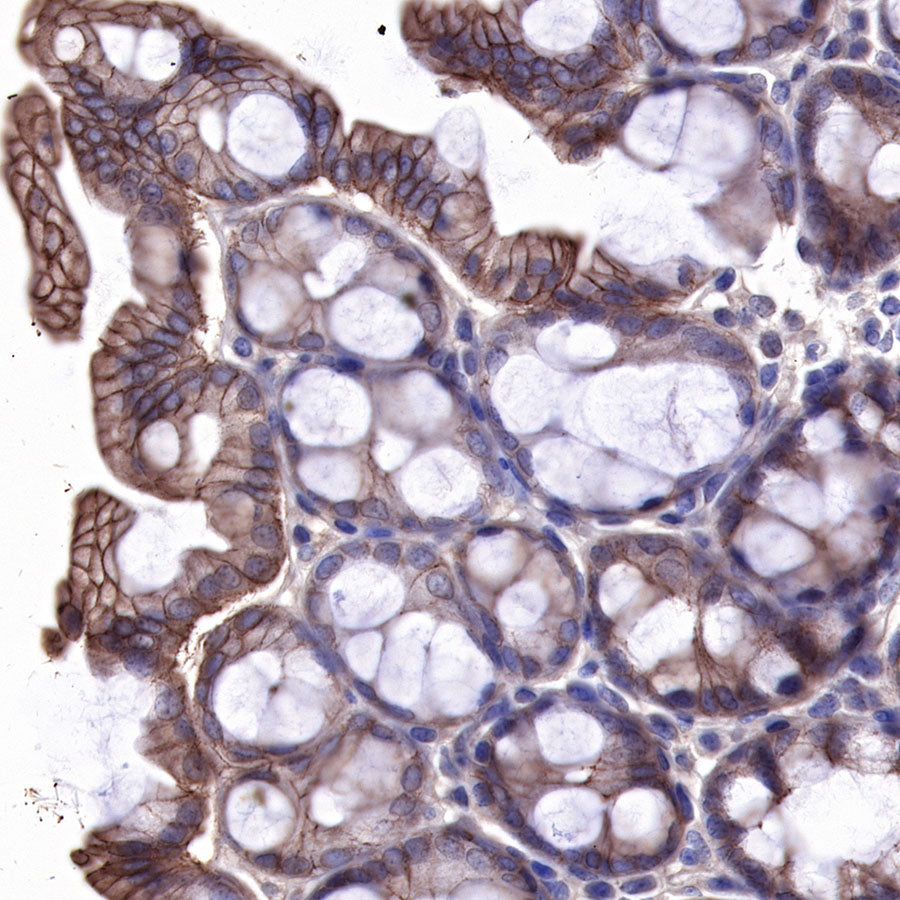

IHC shows positive staining in paraffin-embedded human placenta. Anti-EGFR antibody was used at 1/2000 dilution, followed by a HRP Polymer for Mouse & Rabbit IgG (ready to use). Counterstained with hematoxylin. Heat mediated antigen retrieval with Tris/EDTA buffer pH9.0 was performed before commencing with IHC staining protocol.